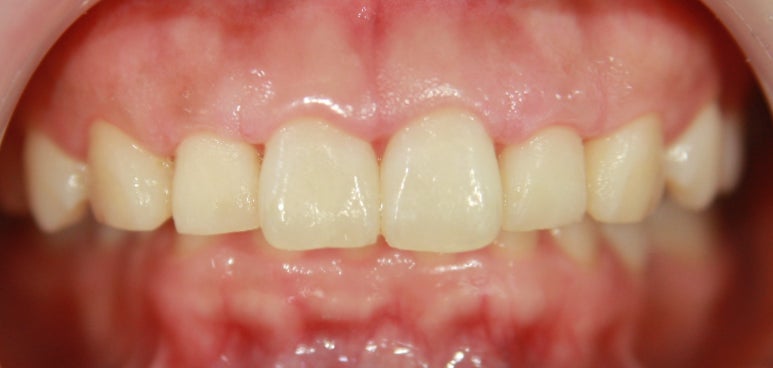

치아 교정

3D 스캔 투명교정으로 간편한 교정치료를 제공합니다.

치아 교정 치료는 기능성과 심미성이 적절한 조화가 이루어져야만 성공적인 치아 교정이라 할 수 있습니다.그렇기에 실력있는 의료진이 축적된 노하우와 기술로 부작용을 최소화하여 환자가 원하는 이상적인 치료 결과를 만들어 내야 합니다. 개인마다 식습관, 치아의 배열, 얼굴의 형태, 라이프스타일 등 전부 다 각기 다르므로 이 모든 항목들을 꼼꼼하게 체크한 후 개개인에게 맞는 맞춤 진단이 필요합니다.